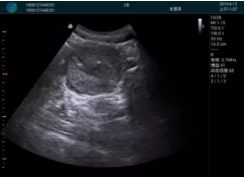

清晰顯示孕囊,通過軟件包計算孕齡7w+6d

M20實時引導(dǎo),術(shù)中清晰顯示孕囊被破壞和抽吸針的過程,清晰顯示吸引針

抽吸結(jié)束后縱切子宮,孕囊已被完全抽吸,未見明顯殘留